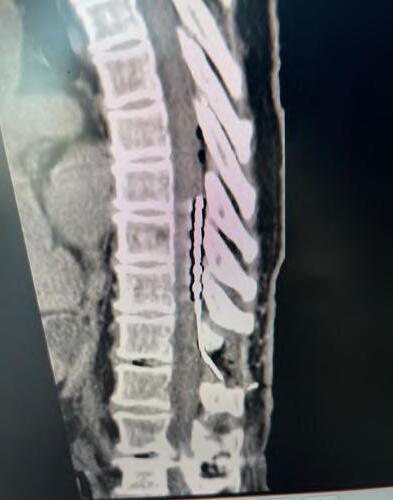

En enero de 2025, el equipo de columna de Clínica Bupa Santiago realizó una cirugía para el tratamiento de dolor crónico intratable, mediante la implantación de un estimulador medular de última generación. El procedimiento fue liderado por el Dr. Miguel Naranjo, traumatólogo especialista en columna, y marca un hito en el abordaje del dolor lumbar persistente, especialmente en pacientes que han agotado otras alternativas terapéuticas.

La paciente, con antecedentes de dolor lumbar crónico, había sido intervenida hace nueve años con una fijación y artrodesis de columna, sin lograr una resolución completa del dolor pese a múltiples tratamientos. Frente a este escenario, y tras una cuidadosa evaluación, se optó por implantar un estimulador medular como última alternativa terapéutica.

Tecnología avanzada al servicio de la calidad de vida

La cirugía consistió en la instalación de una placa de electrodos sobre la médula espinal, conectada a un generador que se ubicó en la zona abdominal. Este dispositivo emite impulsos eléctricos que bloquean la sensación de dolor antes de que llegue al cerebro, permitiendo una mejora significativa en la calidad de vida del paciente.

«El uso de esta tecnología ha demostrado una tasa de éxito cercana al 95%, siempre que exista una correcta selección de candidatos», explicó el Dr. Naranjo. «Hoy, gracias al trabajo de un equipo multidisciplinario y a los avances en diagnóstico, podemos ofrecer esta opción a pacientes que antes simplemente no tenían solución».